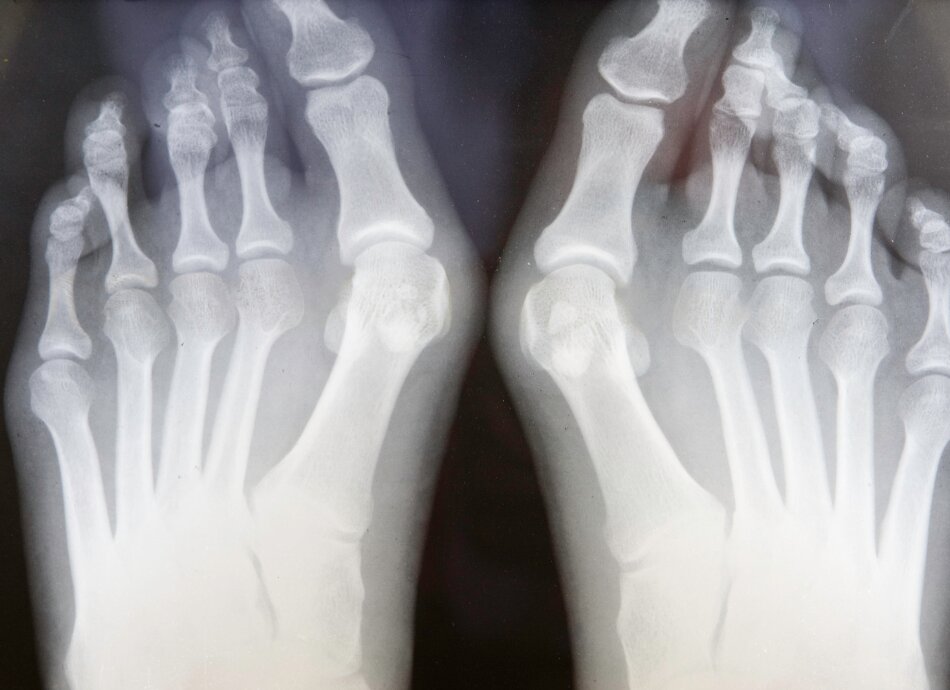

X-ray of bunions on feet

A bunion happens when the bones of your big toe joint get out of line. This makes your big toe lean towards your second toe. Your big toe joint then sticks out more and rubs against the inside of your shoes. This can damage the joint and the skin around it, causing it to become swollen and painful.